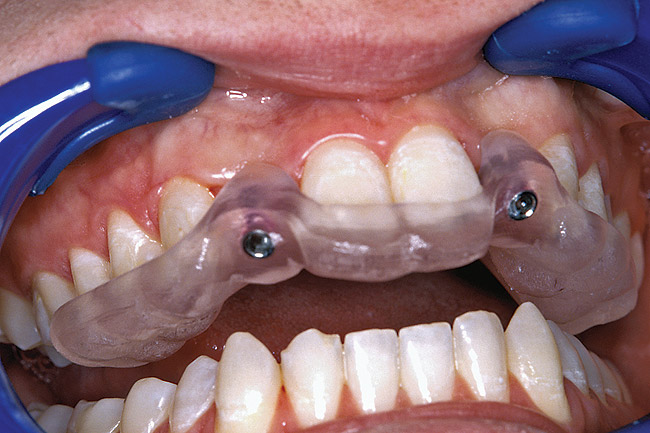

Figure 31  VIRTUAL PLANNING AND SURGERY A surgical template was derived from the final treatment plan created in the software, which facilitated the drilling sequence and precise location of placement.

Figure 31

Figure 32  VIRTUAL PLANNING AND SURGERY A surgical template was derived from the final treatment plan created in the software, which facilitated the drilling sequence and precise location of placement.

Figure 32

Before the day of surgery, the patient was seen by the orthodontist for the removal of the orthodontic brackets. The patient still was not pleased with the position of the two centrals, and it was determined that this would be addressed after implant placement (Figure 26). The anatomical variations of the crestal tissue and lack of interdental papilla can be appreciated in the close-up views of the right and left sites (Figure 27 and Figure 28). There were no surprises on the day of surgery as all of the decisions were made during the planning phase, before the scalpel ever touched the patient. The occlusal view of the CT 3D model revealed the wider alveolar ridge on the right side and thinner crest on the left side (Figure 29). This was confirmed when the full-thickness mucoperiosteal flaps were elevated, and the underlying bone revealed (Figure 30). The tooth-borne templates were designed to facilitate the drills and drilling sequence specific to the diameters of the predetermined implants (Figure 31). Each template contained an embedded 5-mm long stainless steel tube, which was approximately 0.2-mm wider than each drill (just wide enough to allow for the drills to rotate freely). Once positioned over the natural teeth, the template was secure and offered precision accuracy in transferring the implant locations from the original software-designed plan, allowing the potential for internal and external irrigation (Figure 32).